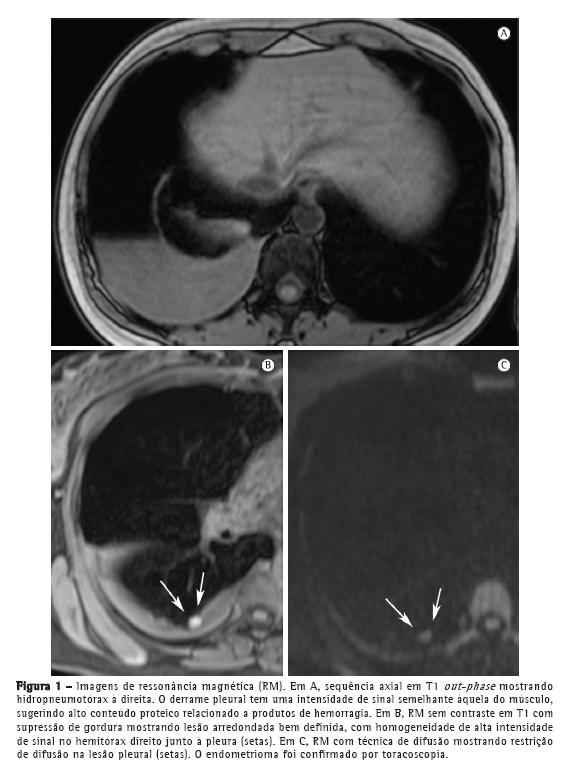

Foi realizada TC, que revelou hidropneumotórax à direita com lesões focais. Na RM de tórax, as sequências T1 e T2 demonstraram hidropneumotórax à direita com pequenas lesões nodulares hiperintensas (Figura 2), sugestivas de endometriomas.

Nos últimos anos, a RM de tórax progrediu muito. Devido a melhorias na velocidade e na qualidade das imagens, a RM está pronta para ser usada na rotina clínica.(7-9) Nos dois casos aqui apresentados, a RM de tórax revelou hidropneumotórax e nódulos arredondados bem definidos na superfície pleural do hemitórax direito. No Caso 1, o derrame pleural apresentou intensidade de sinal intermediária em T1, sugerindo alto conteúdo proteico, provavelmente relacionado a produtos da hemorragia. No Caso 2, o derrame pleural apresentou alta intensidade de sinal, sugerindo hemotórax recente. Os nódulos pleurais observados no Caso 1 mostraram homogeneidade na alta intensidade de sinal em imagens em T1 com supressão de gordura e difusão restrita em imagem ponderada em difusão (IPD). No Caso 2, os nódulos mostraram heterogeneidade na intensidade de sinal nas imagens em T1 e T2, sem restrição de difusão. De forma semelhante à endometriose pélvica,(1,10) os nódulos pleurais da endometriose torácica podem mostrar diferentes intensidades de sinal em imagens em T1 e T2, assim como na variação de restrição de difusão, dependendo da idade da lesão.